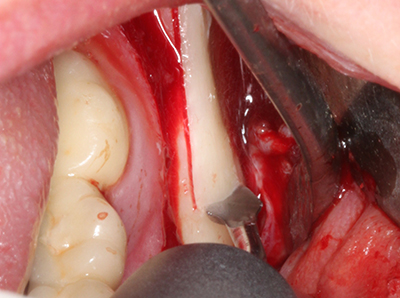

Фиг. 18: Препарация на кортикално покритие с пиезо накрайник за кост (Piezomed, W&H).

Фиг. 19: Хирургичното поле след невролиза и отстраняване на остеотом.

Фиг. 20: Отстраненото костно покритие е поставен отново и фиксиран с винт за остеосинтеза (KLS Martin, Tuttlingen).